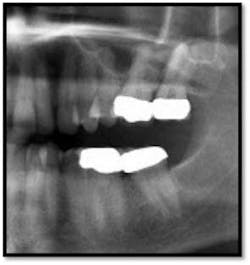

TX FM Perioscopy with local anesthetic FM LANAP Surgical Procedure •bone sounding was performed on all teeth included in this procedure •occlusal adjustment performed resulting in reduction in centric prematurities •Orthodontic referral for anterior spacing •3 month periodontal maintenance14 months post TreatmentPocket reductions of up to 4mm

The patient now has a stable dentition and has moved forward with Invisalign orthodontia to correct the overbite and spacing in her anterior teeth.

The posterior crowns still present a challenge to keep clean and will be scheduled for replacement post orthodontic treatment.

She is enrolled in periodontal supportive therapy every 3 months.